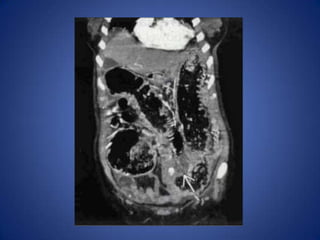

Diverticulitis

• Most common cause in middle-aged and

elderly

– Can affect patients as young as 25

• Usually long ( 10- 1 5 cm) segment of wall

thickening, luminal narrowing, pericolonic

infiltration

• Extraluminal collections of gas or fluid help

confirm diagnosis

Diverticulitis • Most commoncause in middle-aged and elderly – Can affect patients as young as 25 • Usually long ( 10- 1 5 cm) segment of wall thickening, luminal narrowing, pericolonic infiltration • Extraluminal collections of gas or fluid help confirm diagnosis